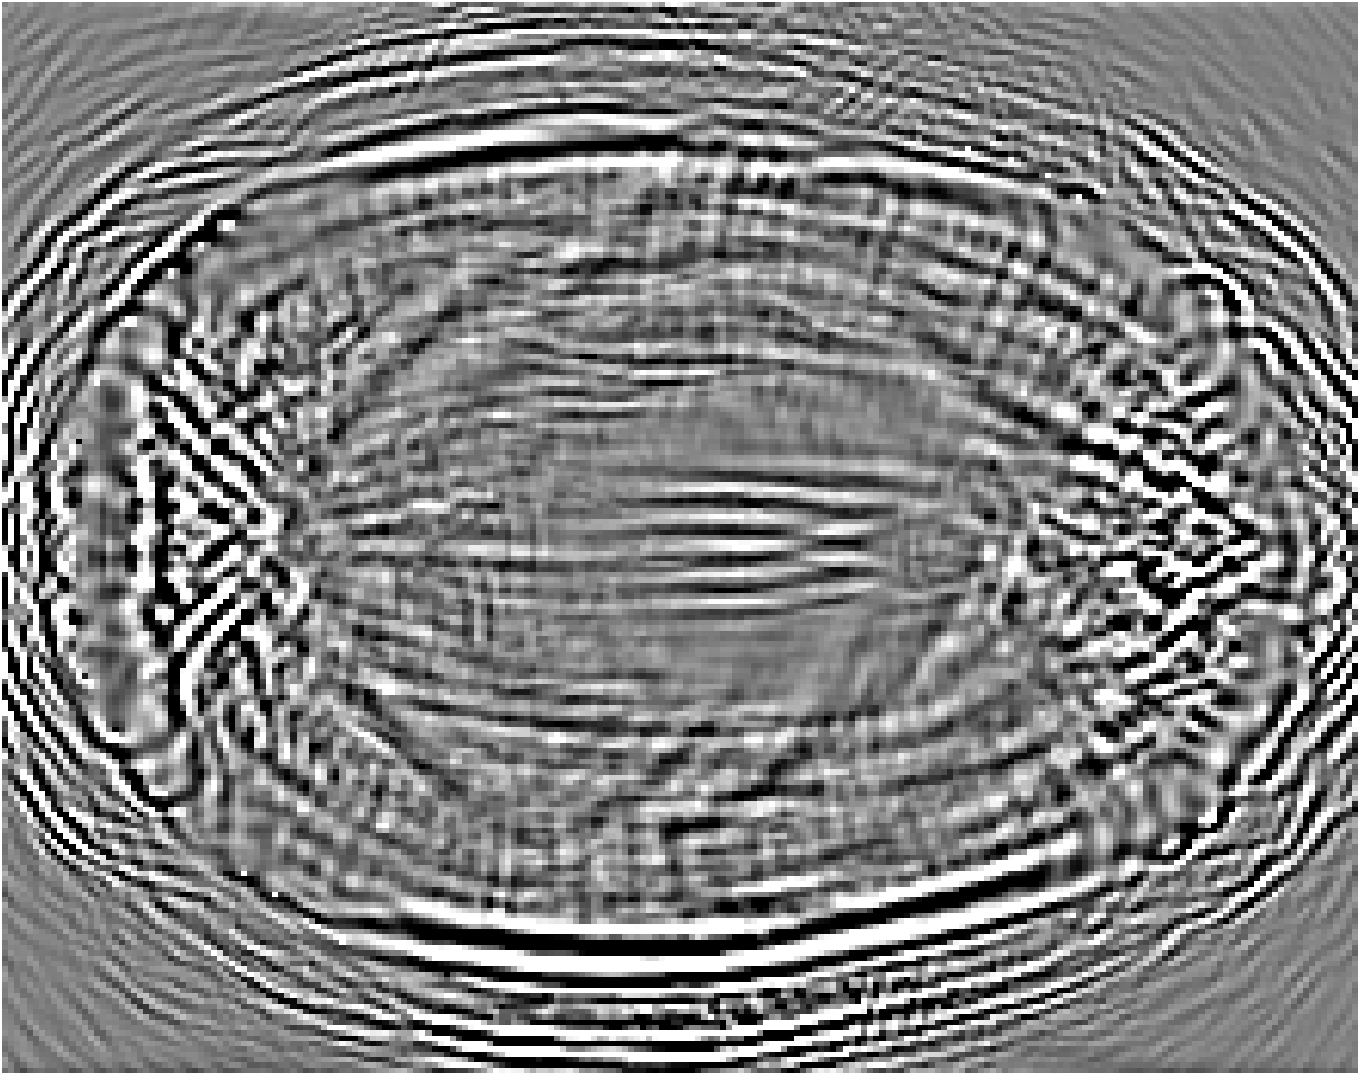

Refer to caption

(a) Partial-transducer dataset

(b) Full-transducer dataset

Figure 8: Stacked TRA Image with (a) Partial-transducer dataset and (b) Full-transducer dataset

To evaluate performance, we construct two acquisition setups from the same horizontal 2D slice of the phantom: (i) an idealized full-transducer dataset (Figure 4(b)) providing near-uniform coverage along the head contour, and (ii) a partial-transducer dataset (Figure 7) designed to reflect practical acquisition constraints. In the partial setup, a linear array with 51-element is repositioned around the head; for each view, the central element transmits and all other 50 elements receive. The partial setup includes 50 sweeps covering the full 360, meaning that for each sweep, the source and receivers rotate by 360/50=7.2360/50=7.2^{\circ}. Sweeping 50 views yields, per 2D slice, a channel tensor of shape (T,Ns,Nr)=(5001,50,50)(T,N_{s},N_{r})=(5001,50,50). The key distinction between these two datasets is their aperture: full-transducer provides near 360 coverage in a single placement, whereas partial-transducer attains coverage by aggregating neastest 50 receivers in a single placement, which is only around 36. Particularly, the partial-transducer setup includes only 50 sweeps, while the full-transducer setup uses all receivers covering the entire brain, with each transducer acting as a source in turn while the others serve as receivers. Compared to the full-transducer, the partial-transducer achieves coverage by combining a much smaller number of views. For each sweep, we generate the forward wavefield g(𝐱,t|𝐠){{g}}(\mathbf{x},t|\mathbf{g}) and the back-propagated wavefield p~(𝐱,t|𝐠)\tilde{{p}}(\mathbf{x},t|\mathbf{g}) and generate the TRA fragment with Eq. (7) (example in Figure 7). With the physical TRA method, the TRA fragment can be stacked to give the stacked TRA image. To validate the differences between the two datasets, we generated stacked TRA images using both datasets, as shown in Figure 8. As shown in Figure 8(b), the full-transducer dataset provides significantly greater detail in internal structures. Despite higher levels of noise and artifacts caused by the limited number of views, the partial-transducer dataset is still capable of capturing some meaningful tissue structures.